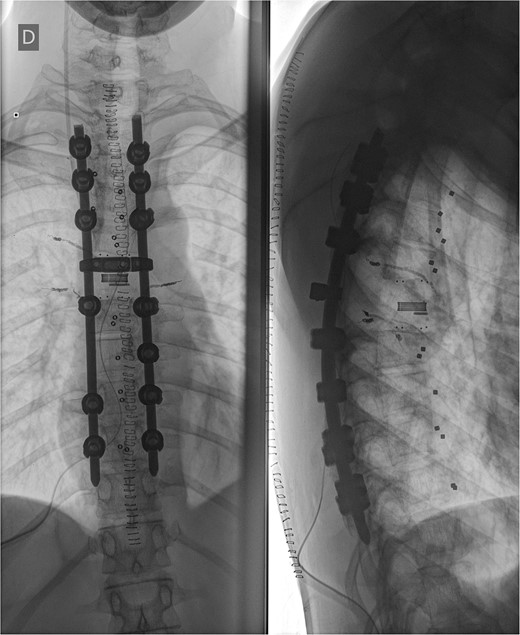

Three and a half years prior to admission to our institution, the patient underwent emergent Th6 vertebroplasty with laminectomy for a radiologically characteristic and histologically confirmed Th6 AVH causing acute thoracic myelopathy with a week-long paresis of the right foot dorsiflexion, performed by another surgeon. A progressive kyphotic deformity of the Th6 vertebrae was observed on radiographic follow-ups, whereby the hypoesthesia on the right anterior thigh persisted (ASIA score D, VAS pain score 7). Follow-up MRI and CT imaging revealed recurrent AVH of the Th6 vertebrae expanding into the spinal canal, leading to newly recognized worsening of myelopathy (Fig. 1). Additionally, a concomitant haemangioma was observed in the right transverse and articular process of Th8 (Fig. 2).

Follow-up CT imaging revealed recurrent AVH of the Th6 vertebrae, MRI scan showing AVH expanding into the spinal canal and causing myelopathy.

MRI scan of the thoracic spine showing a concomitant haemangioma in the right transverse and articular process of Th8.